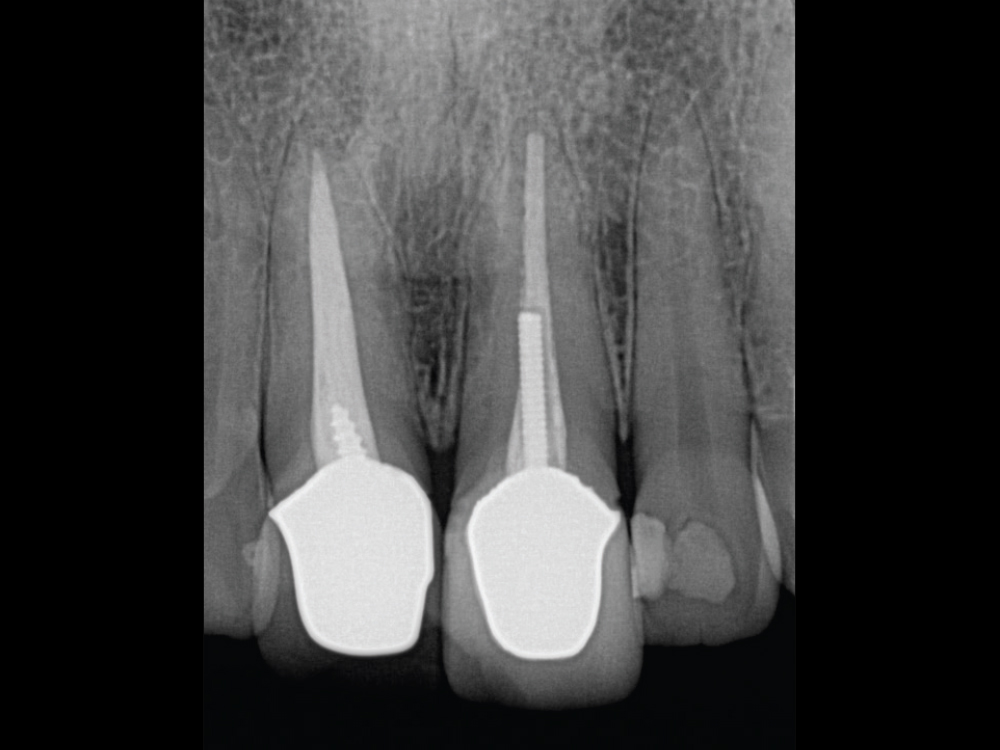

Life-like esthetic restorations

Scanner view of abutments

Four months after the surgical procedure, gold-tone custom abutments and all-ceramic crowns were delivered. The custom abutments and implant crowns were produced for a reduced fee because of the 20% discount offered by Glidewell for restorations over Hahn implants. The final restorations achieved esthetic, lifelike emergence profiles due to the soft-tissue management provided by the immediate provisional restorations during the healing phase. Note the crestal bone levels around the Hahn implants.